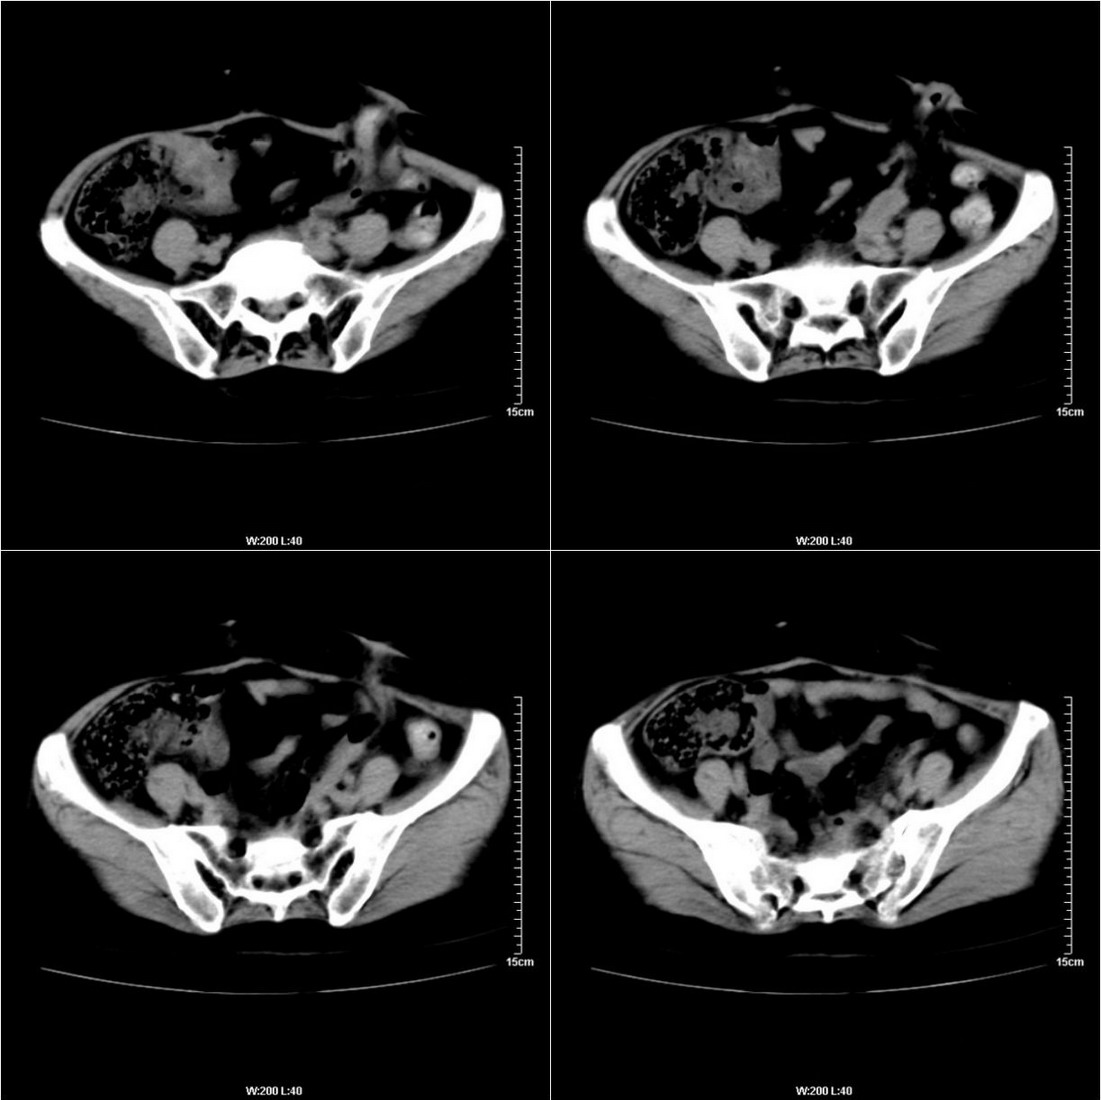

不知道病人的直肠癌手术方式如何,直肠已经全部切除,乙状结肠造瘘于左下腹,肛门应该也没有保留吧?如此,应该是复发了:

病变于肛尾韧带、右侧坐骨肛门窝内并顺右侧肛提肌向右侧闭孔内肌蔓延,骶前软组织内也形成了肿块,麻烦啊!

典型直肠癌术后骶骨前转移复发.

膀胱壁见索条状软组织密度影伴强化,可考虑炎性肉芽肿样增生改变,常见于放疗后或慢性感染;直肠及周围软组织见肿块,轻度强化,考虑直肠癌术后复发,并侵犯周围组织

考虑直肠癌术后复发并侵犯周围组织。

直肠癌术后人工肛门,骶前及术区结节及囊状影,强化不明显,考虑术后瘢痕及粘连包裹可能大,转移不除外。